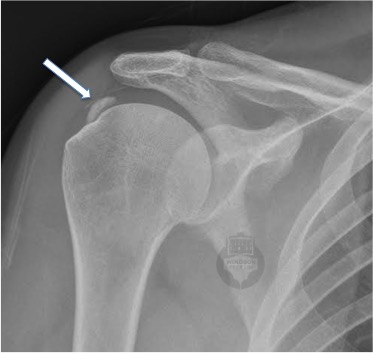

🔍 What We See on Scans

- X-rays are excellent for showing the location, size, and stage of the deposit.

Remember: the amount of calcium doesn’t always match the amount of pain. A small deposit can be very painful if it’s inflamed, and a large one might be completely silent.